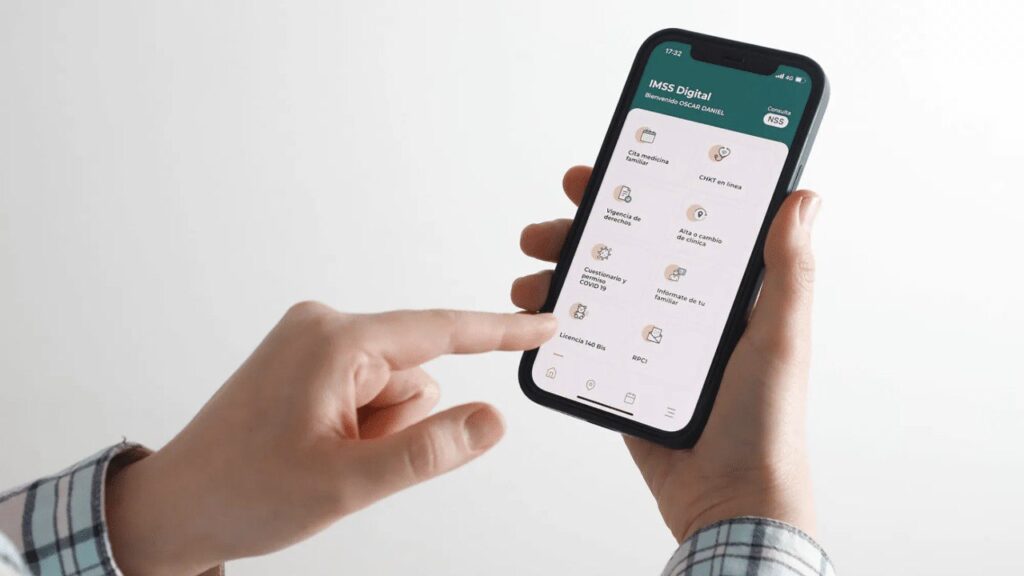

Expediente Digital de Salud para alumnos de primaria ya está disponible: ¿Qué es y cómo consultarlo?

Las Jornadas de Salud Escolar arrancaron en 90 mil 832 primarias públicas del país, en beneficio de 12 millones de estudiantes en total, con el apoyo de brigadistas que tuvieron la tarea de medir peso y talla, evaluar agudeza visual, revisar salud bucal y realizar pláticas sobre hábitos saludables.